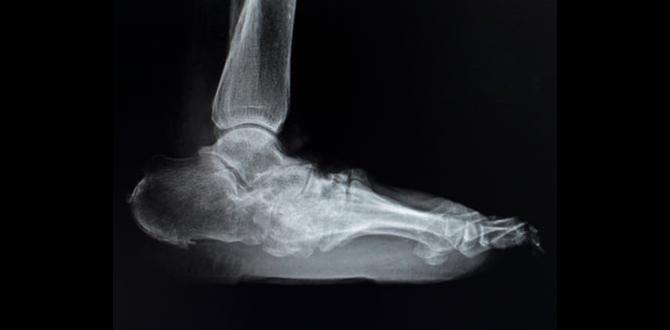

Charcot foot insoles play a vital role in managing the condition of Charcot foot. This condition causes weakening of bones in the foot, leading to severe deformities. Proper insoles support the foot’s structure and alleviate pain. They also help in redistributing weight, preventing further damage. Did you know that using the right insoles can improve your balance? By choosing the right type, you can walk better and feel more comfortable every day.What is Charcot Foot?

Definition and description of Charcot foot.. Common causes and risk factors associated with the condition..Charcot foot is a serious condition that affects the bones in the foot. It happens when there is damage to the nerves. This can lead to swelling, pain, and changes in the foot shape. Common causes include diabetes, nerve injuries, and arthritis. Risk factors can be: